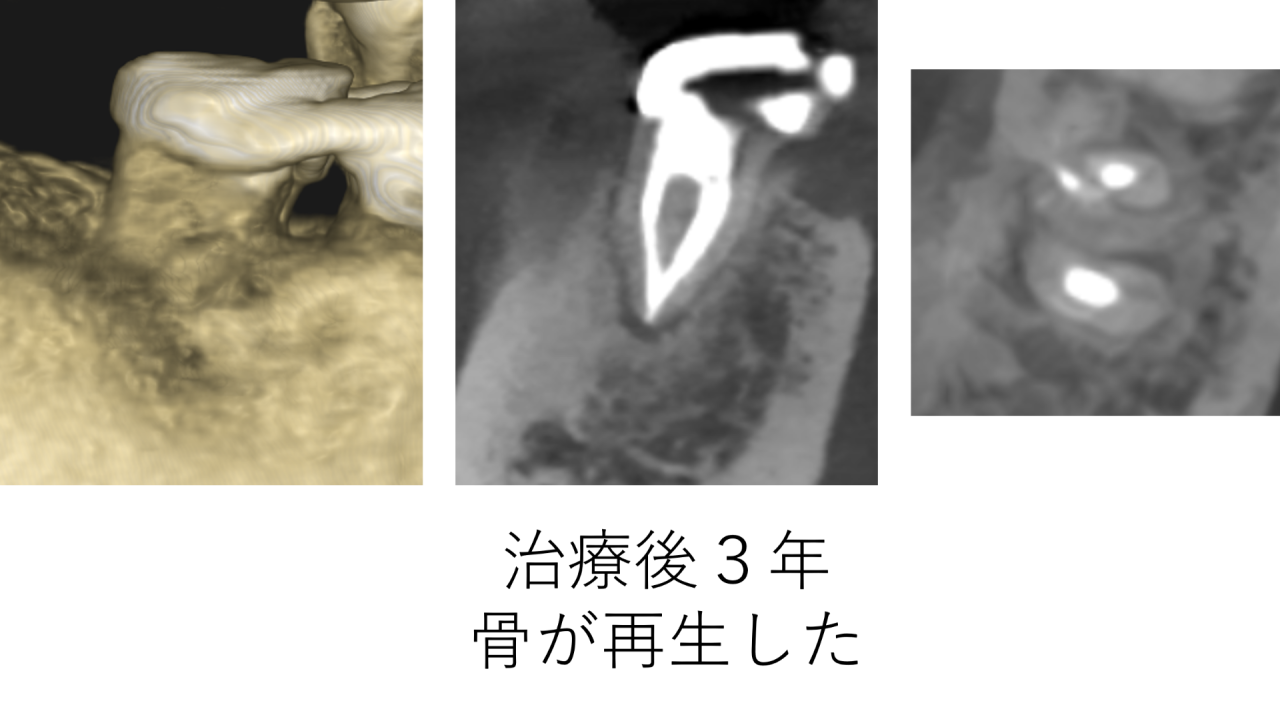

治療して3年後のレントゲンです。大きく溶けていた骨が再生し、ほとんど全て治っていました。大きく開いていた穴も、すべて塞がりました。

骨を溶かすのは細菌です。治療で、取り残されて腐ってしまった神経を取り、細菌を取り除いたことによって、患者様の持つ免疫力が骨を再生させました。

このように、精密な根管治療を行えば大きく溶けた骨が再生することもあります。